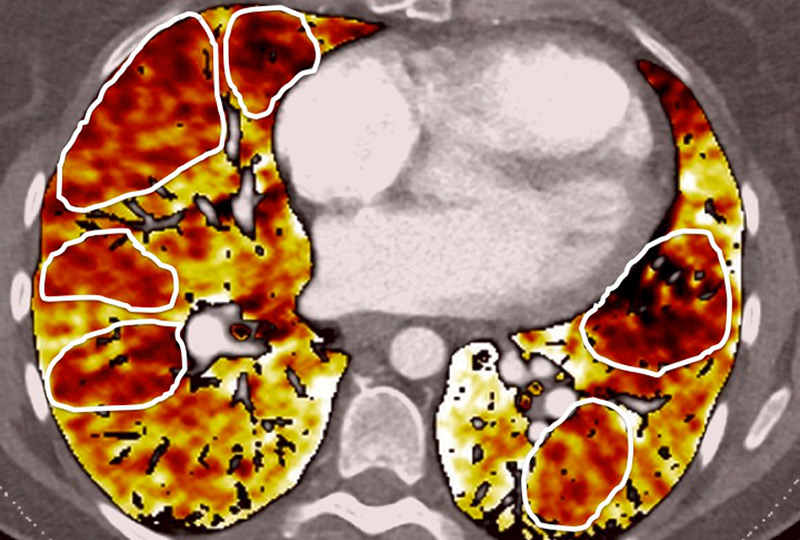

Figure 6

Perfusion heterogeneities in idiopathic pulmonary artery hypertension (stars) in two different patients (A/B). The dilatation of the arteries in pulmonary hypertension (arrows) is not always observed depending on the severity of pulmonary hypertension.